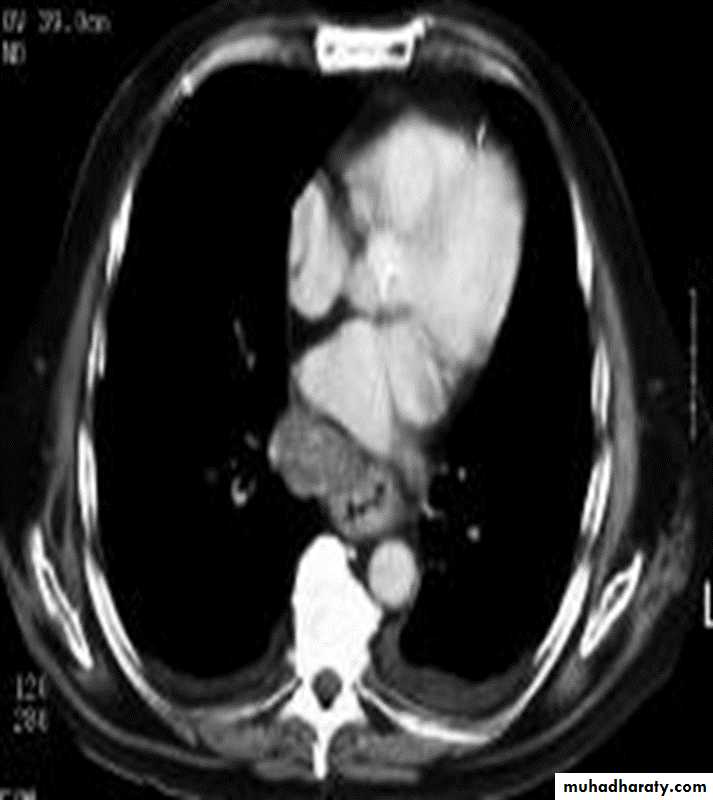

Computed Tomography

Contrast-enhanced CT plays an important role in the1.staging of esophageal carcinoma.

2.determining the extent of the local tumor

3.invasion of mediastinal structures

4.involvement of supra clavicular, mediastinal, or upper abdominal lymph nodes

5. Assessment of the distant metastases

examination should extend from the thoracic inlet through the liver

CT essential in the Dx & staging of the CA

CT finding of esophageal malignancy

1.Eccentric or circumferential wall thickening is greater than 5 mm.

2.Peri-esophageal soft tissue and fat stranding may be demonstrated.

3.A dilated fluid- and debris-filled esophageal lumen is proximal to an obstructing lesion.

4.Aortic invasion .

5.Osophageal CA is often metastatic at the time of presentation ( look for the LN & distal metastasis ) .